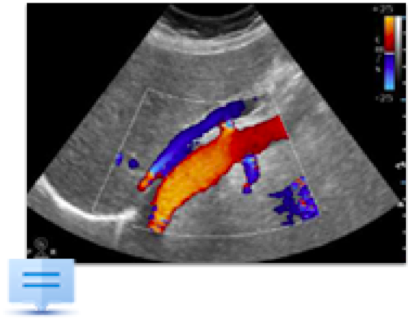

L’ECOGRAFIA NELLA VALUTAZIONE DELL’ACCESSO VASCOLARE PER DIALISI Bari – 28 e 29 novembre 2017 PROGRAMMA